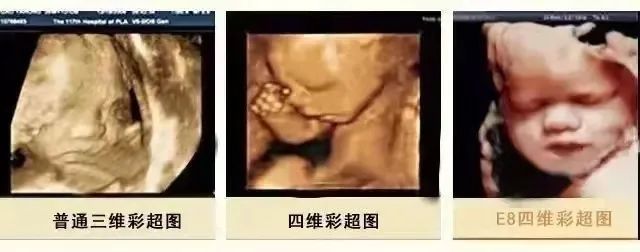

E8在设计上采用接触人体工程学设计模式,不存在射线、光波和电磁波等方面的辐射,对孕妇和胎儿发育没有任何影响,胎儿畸形筛查、成像效果遥遥领先于其他设备,超越了普通四维彩超的局限性,能够更全面、更精确地检测胎儿的生长发育状况、胎盘环境、子宫状况等,显像更清晰立体,形象逼真。

(美国GE-E8高清四维彩超)